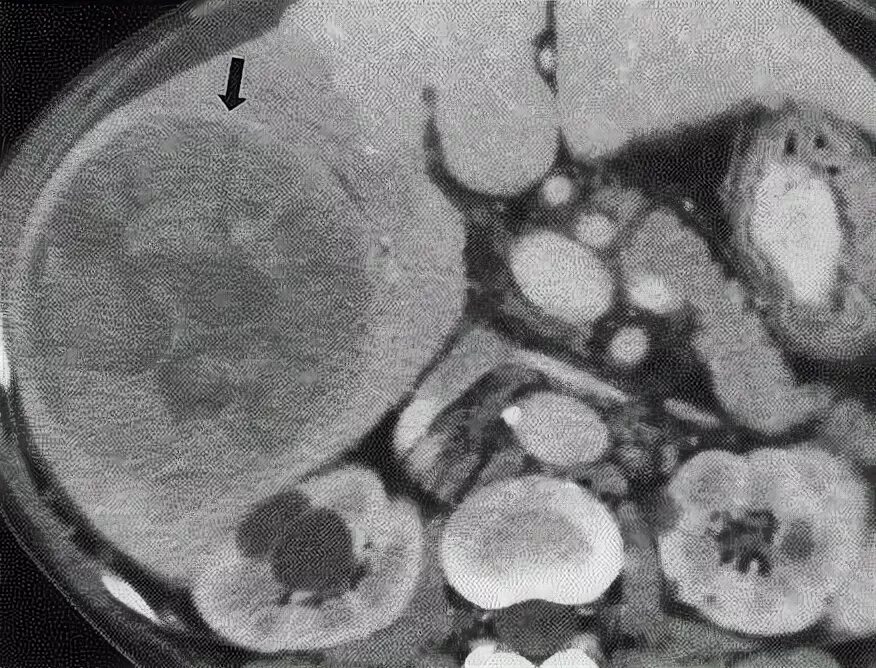

Метастазы печени какие